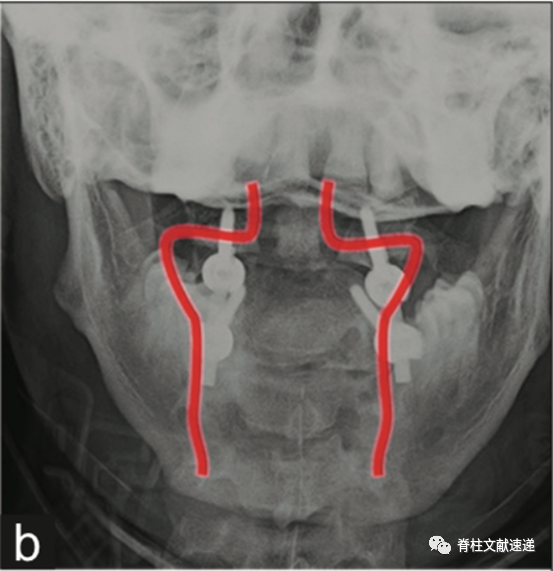

安装螺钉之后,进行正侧位C臂透视,四枚螺钉都有内倾角度。C1螺钉较C2螺钉偏外。安装连接棒进行矫形。(红线:椎动脉大致走行)。